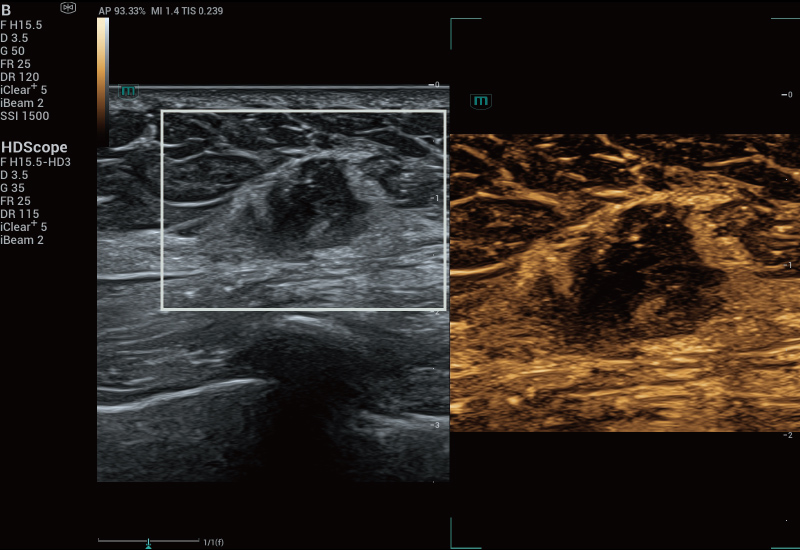

STVi consente la valutazione quantitativa della viscosit├Ā dei tessuti e fornisce immagini multiparametriche in tempo reale, offrendo un approccio pi├╣ completo alla diagnosi per immagini e all'analisi quantitativa di malattie epatiche croniche, lesioni mammarie e altre condizioni.

Coefficienti quantitativi doppi

Valutazione della malattia epatica cronica

Strumenti di quantificazione multipli

Valutazione del tumore al seno